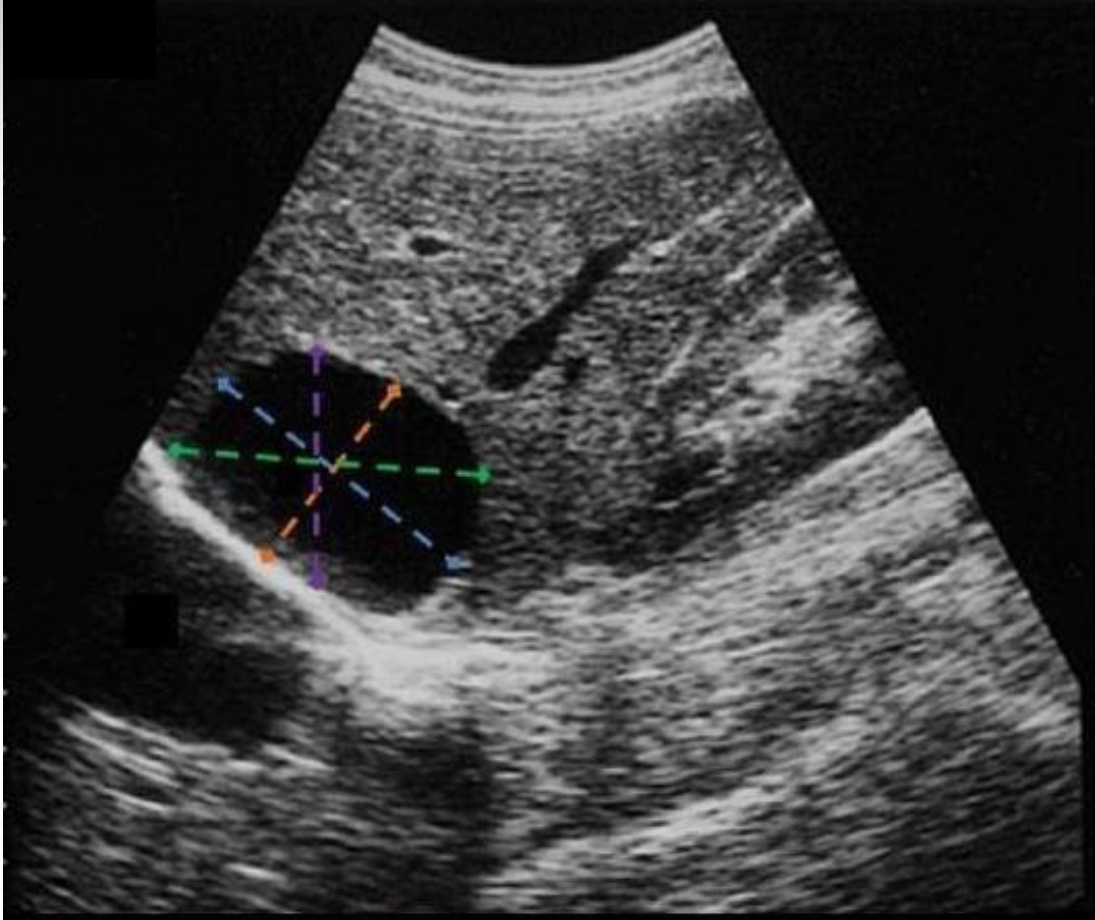

Which line indicates the correct length measurement of the liver cyst?

Blue

Which line indicates the correct AP measurement of the liver cyst

Orange